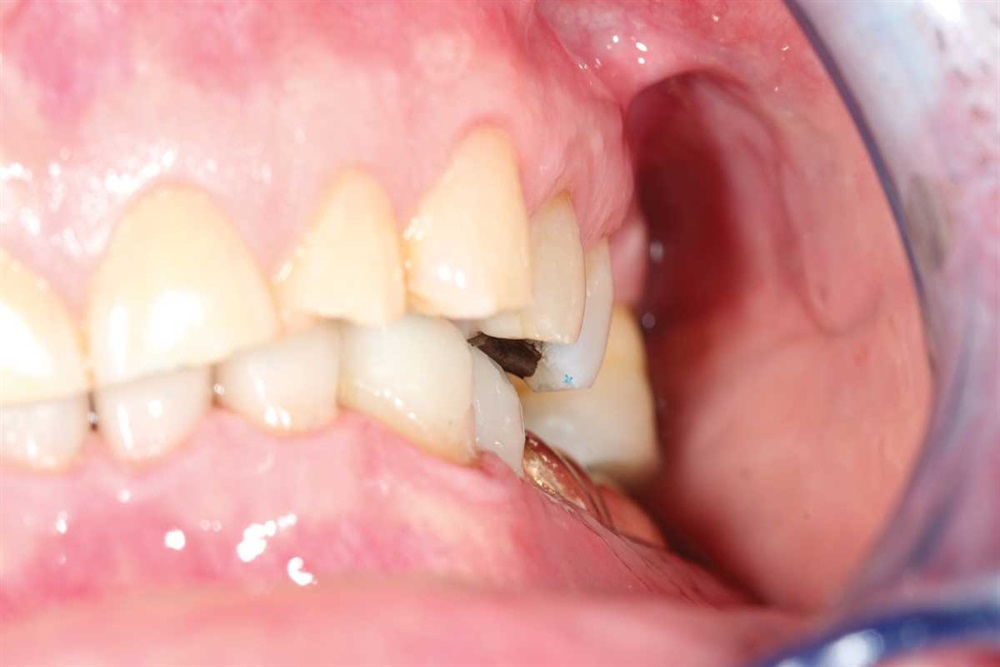

Fig. 1: June 2018. Where did all the tooth structure go? Grinding in protrusion? There is serious wear and tear. This 63-year-old gentleman has been wearing out his teeth, especially in the past 10 years.

Fig. 3: Lower incisors. The patient’s dentists in Ontario wanted to do ortho for 18–24 months and then restorative crowns with many elective root canals, to the tune of a nice luxury car.